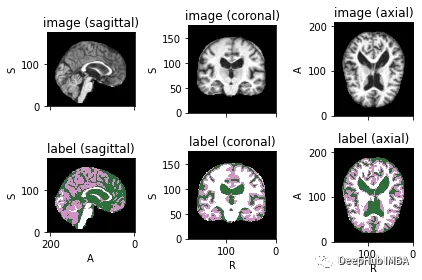

为了可视化带有相应标签的图像,可以使用TorchIO,这是一个Python库,用于深度学习中多维医学图像的加载、预处理、增强和采样。

image\_filename \= root\_dir + '/Oasis\_Data\_Processed/OAS1\_0001\_MR1\_mpr\_n4\_anon\_111\_t88\_masked\_gfc.nii'

label\_filename \= root\_dir + '/Oasis\_Labels\_Processed/OAS1\_0001\_MR1\_mpr\_n4\_anon\_111\_t88\_masked\_gfc\_fseg.nii'

subject \= torchio.Subject\(image\=torchio.ScalarImage\(image\_filename\), label\=torchio.LabelMap\(label\_filename\)\)

subject.plot\(\)